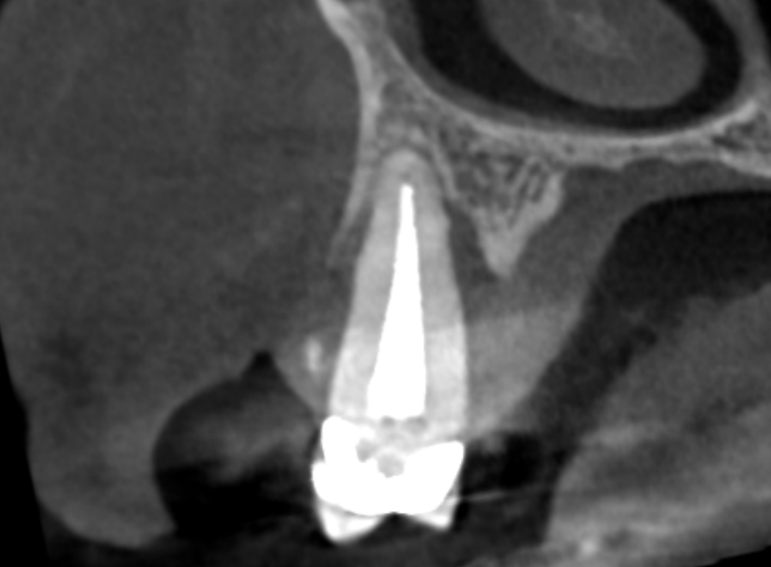

Case 24 – Endodontics

Transillumination after trauma